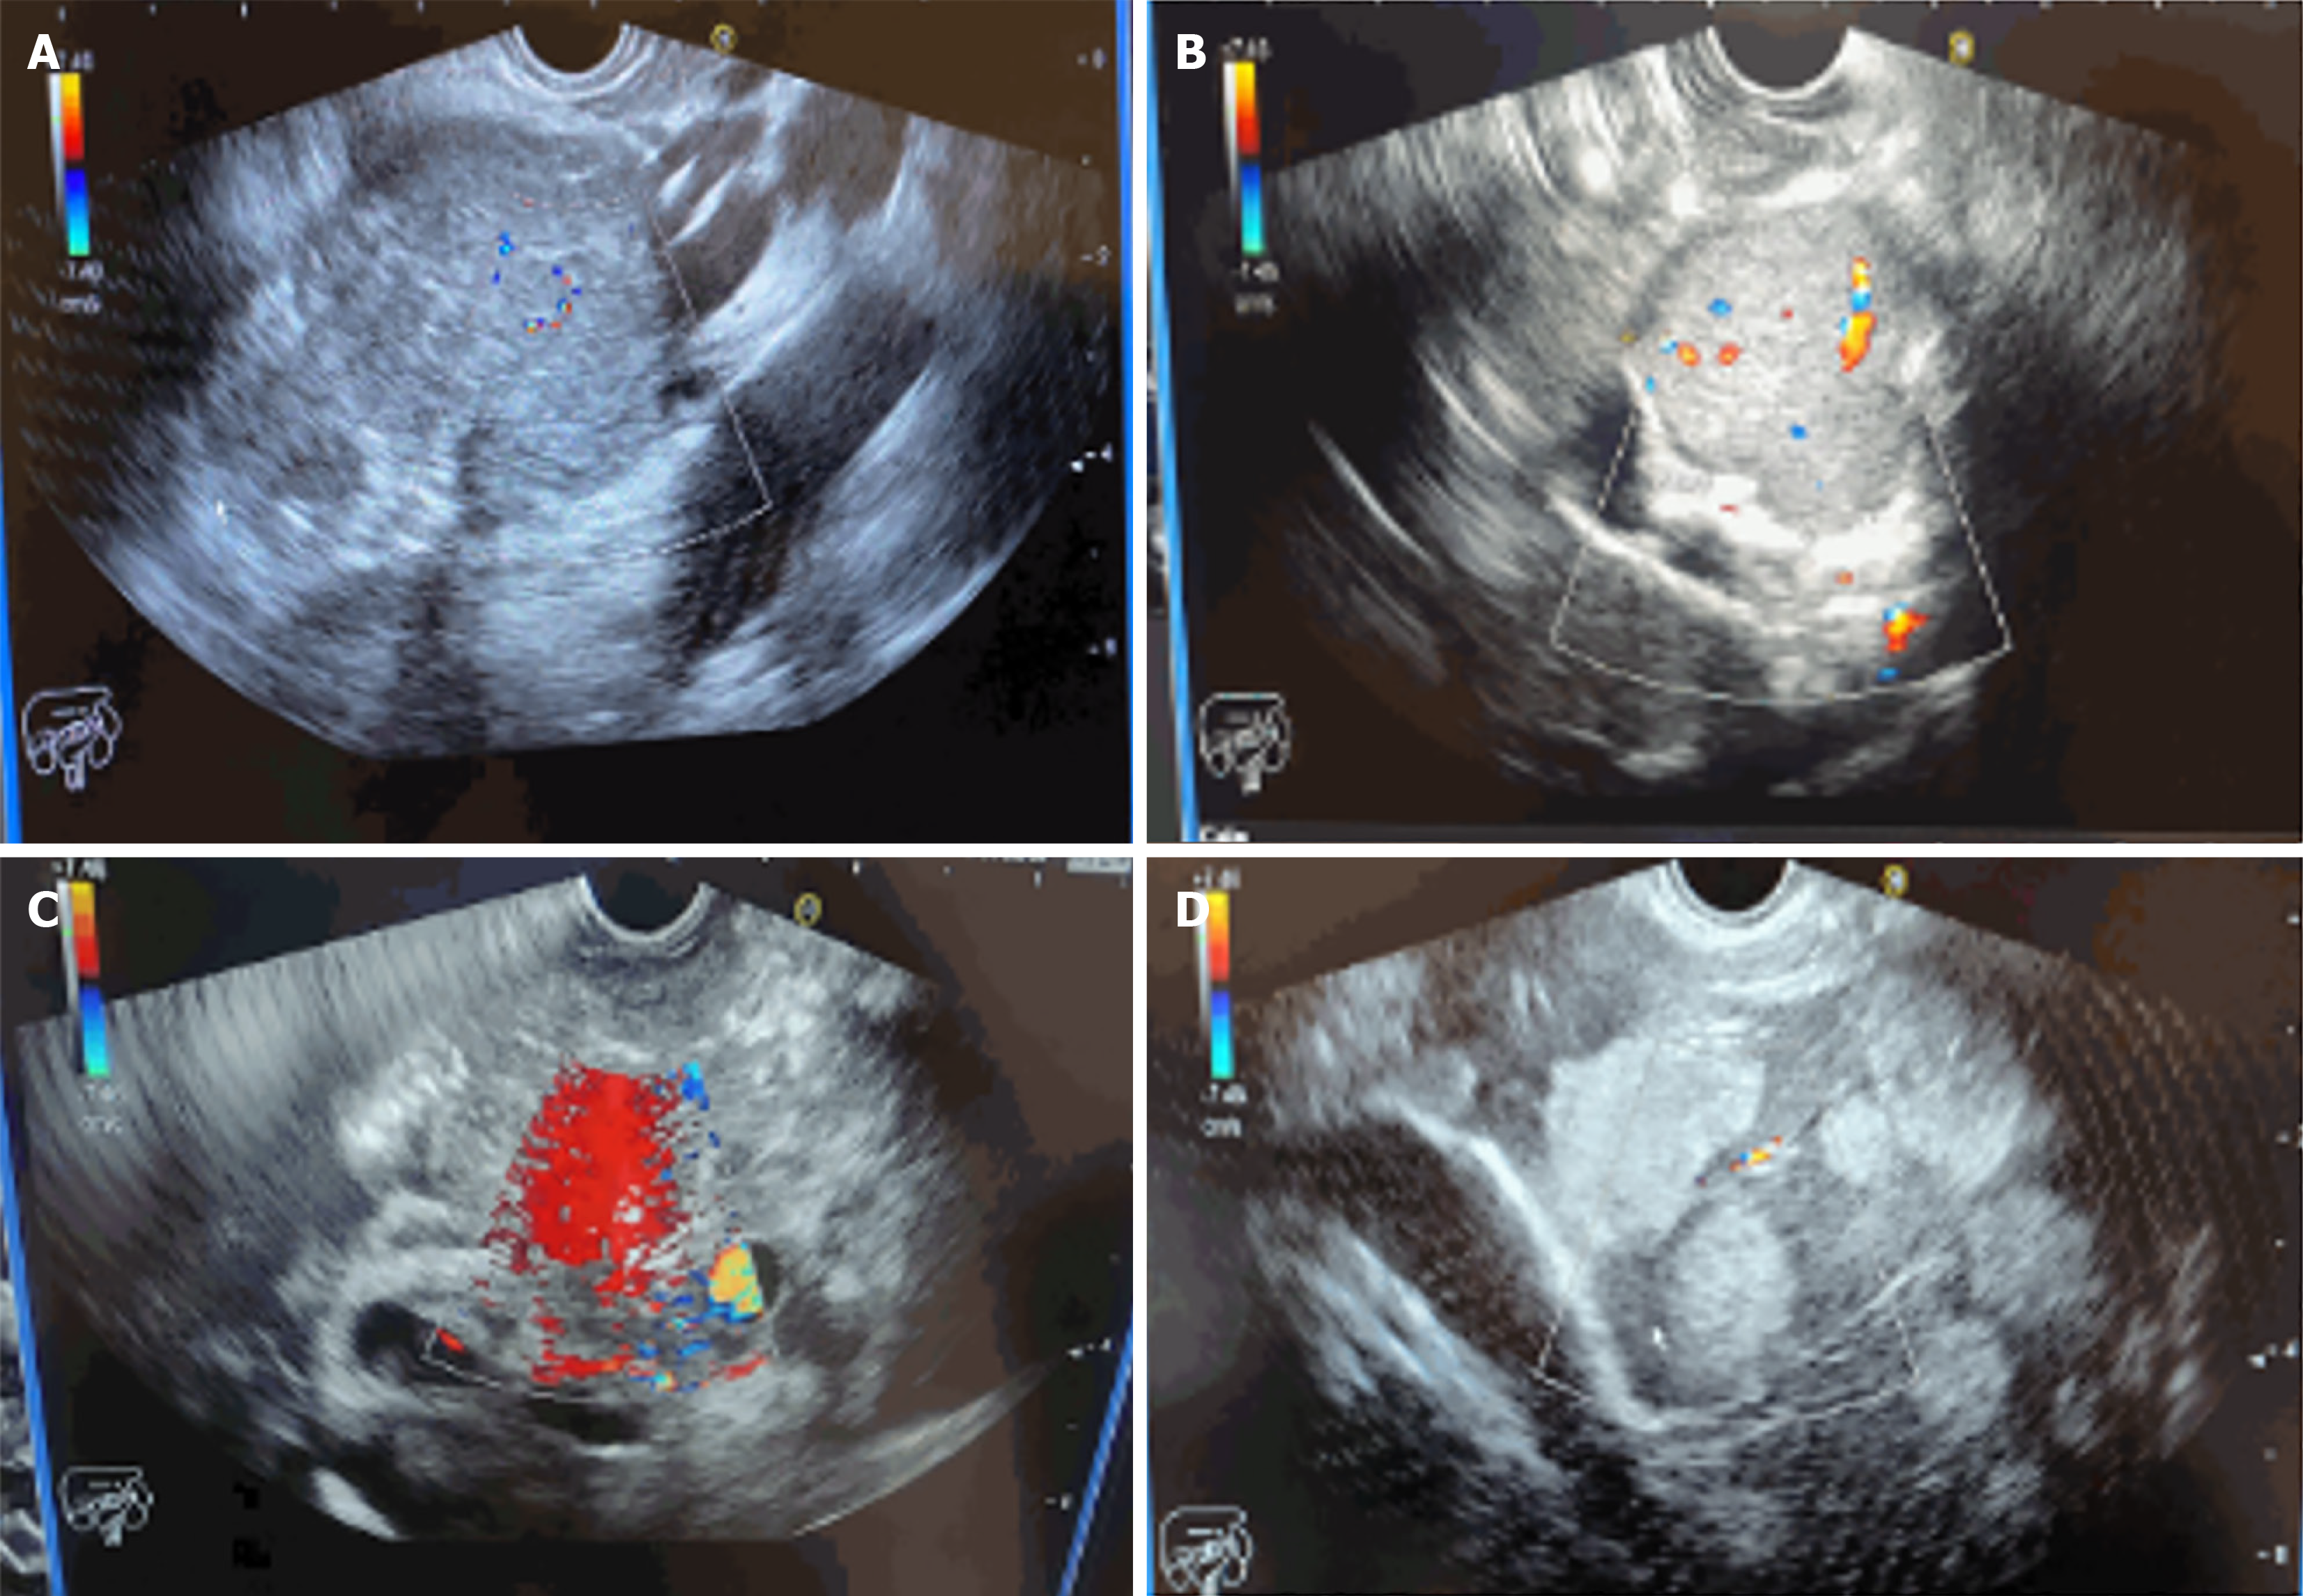

Initially, 13 out of 14 patients (92.9%) underwent CT scans, while the remaining 1 patient underwent esophagogastroduodenoscopy (EGD). Lesions were successfully detected in all patients, indicating the need for EUS to be performed for a definitive diagnosis. CT scan findings showed a pancreatic mass in 6 out of 14 patients (42.9%). Additionally, pancreatic cyst was detected in 1 patient (7.1%). Among the 6 patients with detected pancreatic mass, liver metastatic lesions and lymphadenopathy were each observed in 1 patient (7.1%). In one patient (7.1%) who underwent EGD, an extrinsic mass compressing the pyloric area was detected. Subsequently, all patients underwent EUS guided fine needle biopsy (FNB) procedure in conscious state without any complications and achieved a 100% diagnostic yield (Table 2, Figure 1).

In our study, the pancreas was identified as the most common tumor site, with 8 patients (57.1%) affected. This was followed by porta hepatis, where 2 patients (14.3%) had tumors (Figure 2A). Among the patients diagnosed with pancreatic tumors, 5 out of 7 patients (57.1%) had lesions in the head of the pancreas, whereas 2 patients (28.6%) had lesions in the pancreatic tail, and 1 patient (14.3%) had lesions in both the body and tail of the pancreas. Out of 14 patients, 8 patients (57.1%) had GEP-NETs that metastasized to other sites. Among these tumors, the most common site of metastasis was the liver, with 5 patients (35.7%) affected, followed by the duodenum, which was affected in 2 patients (14.3%; Figure 2B).

Histopathological diagnosis was established utilizing immunohistochemistry (IHC) and morphological evaluation (Figure 3). Out of 14 patients, tumor cells from 13 patients (92.9%) were found to be positive for cytokeratin AE1/AE3 staining, while synaptophysin staining was positive in all 14 patients. Among 6 patients (42.9%), CGA staining was performed, and 5 out of these 6 patients (35.7%) showed positive results. The Ki-67 index was assessed in all 14 patients, with 8 graded as G2 (57.2%), 3 as G3 (21.4%), and 3 as G1 (21.4%). Final histopathology analysis showed a higher prevalence of WD-NETs, found in 11 out of 14 patients (78.6%). In contrast, poorly differentiated tumors were seen in 3 patients (21.4%). Among the WD-NETs, further subclassification into grades showed that the majority were grade II, observed in 6 out of 14 patients (42.9%), followed by grade I in 4 patients (28.6%) and grade III in 1 patient (7.1%). For the poorly differentiated tumors, the majority were of the small cell type, found in 2 patients (14.3%), with one case (7.1%) being of the large cell type (Table 3).